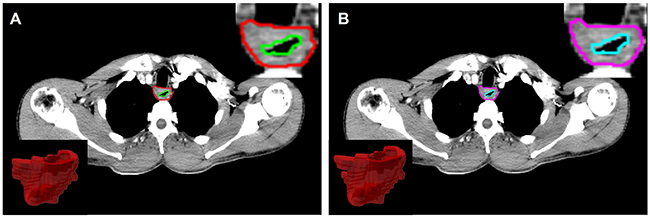

All planning CT scans were obtained from the same CT scanner (Philips Brilliance 6; Philips Healthcare, Best, the Netherlands) according to a standard clinical acquisition protocol (tube voltage, 120 kVp; tube current, 200 – 250 mAs; rotation time, 0.75 s ; pitch, 0.9; matrix, 512x512; field of view, 350 mmx350 mm; convolution kernel, standard), following intravenous injection of 300 mg/mL iodinated contrast agent at a rate of 3mL/s. In our database, the imaging slice thickness was 2.5mm or 3mm and the in-plane resolution was 0.97mm by 0.97mm. The primary 3D region of interests (ROIs) were manually delineated slice-by-slice in mediastinal window on Pinnacle software (Philips Medical Systems, Andover, MA) by two expert radiologist (Ren W. for ROI-1 and Li S. for ROI-2) and then reviewed by an experienced radiologist (Yan J.). For each ROI, the contours were drawn around the gross tumor volume (GTV) avoiding air, fat, and bone (Figure 2).

Figure 2: Region of interest (ROI) was contoured by two radiologists, and corresponding 2D/3D ROI (A for ROI-1 and B for ROI-2).